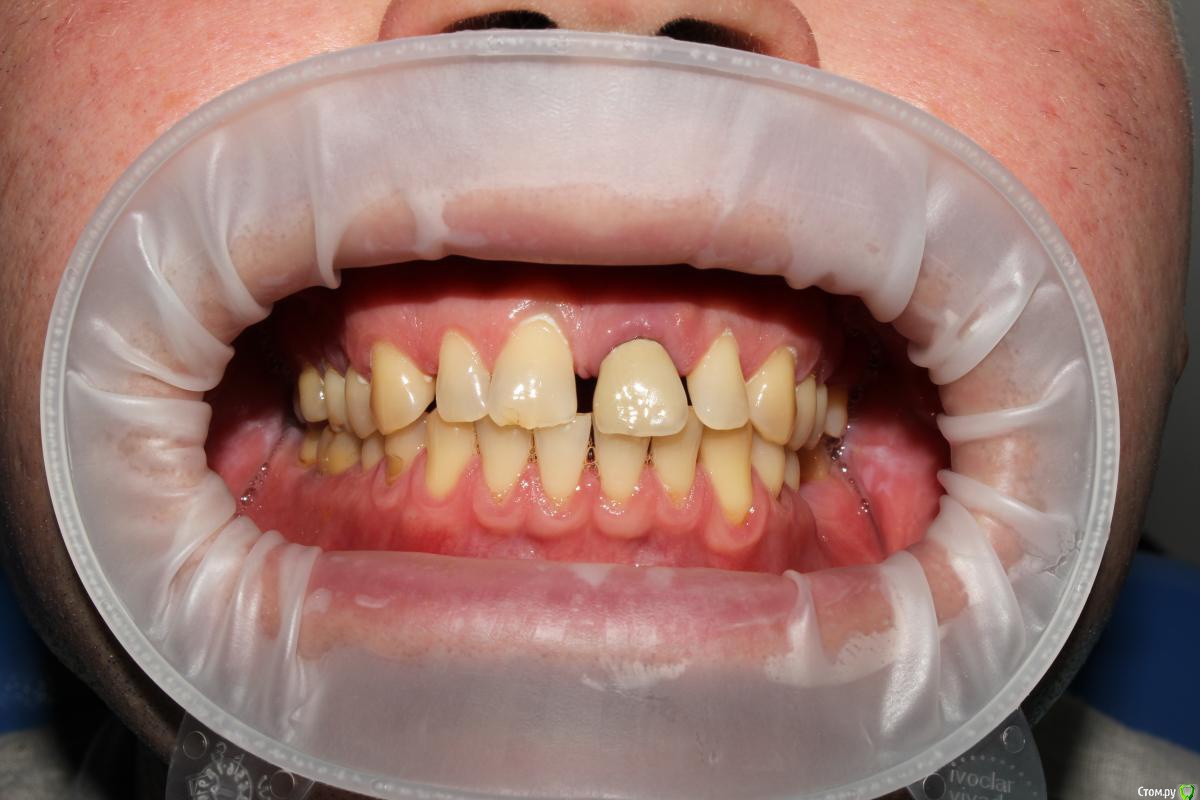

Рустам Опубликовано 20 июля, 2015 Поделиться Опубликовано 20 июля, 2015 Здравствуйте коллеги! Подскажите по клиническому случаю пожалуйста. Обратился пациент в клинику с подвижной коронкой на зубе 2.1, на рентгене диагностирован перелом корня, планируем удаление с одномоментной имплантацией и желательно с немедленной нагрузкой. Система имплантатов "Osstem", на этой системе я ранее не протезировал (работал с "Mis" и "Super Line") и вообще ранее немедленно не нагружал имплантаты. Хирург назначил удаление и иплантацию на 23.07, я смогу принять пациента только 24.07 утром, необходимо заказать временный абатмент, подскажите какой именно из каталога нужно заказать?Имплантолог заказал два имплантата Osstem TSIII SA диаметром 4,0 и 4,5.Я планирую делать временную прямым способом по ключу снятому со старой коронки во рту. Может лучше через оттиск заказать лабораторную временную?P.S. пациента эстетически все устраивало, ортодонтию не хочет. Ссылка на комментарий